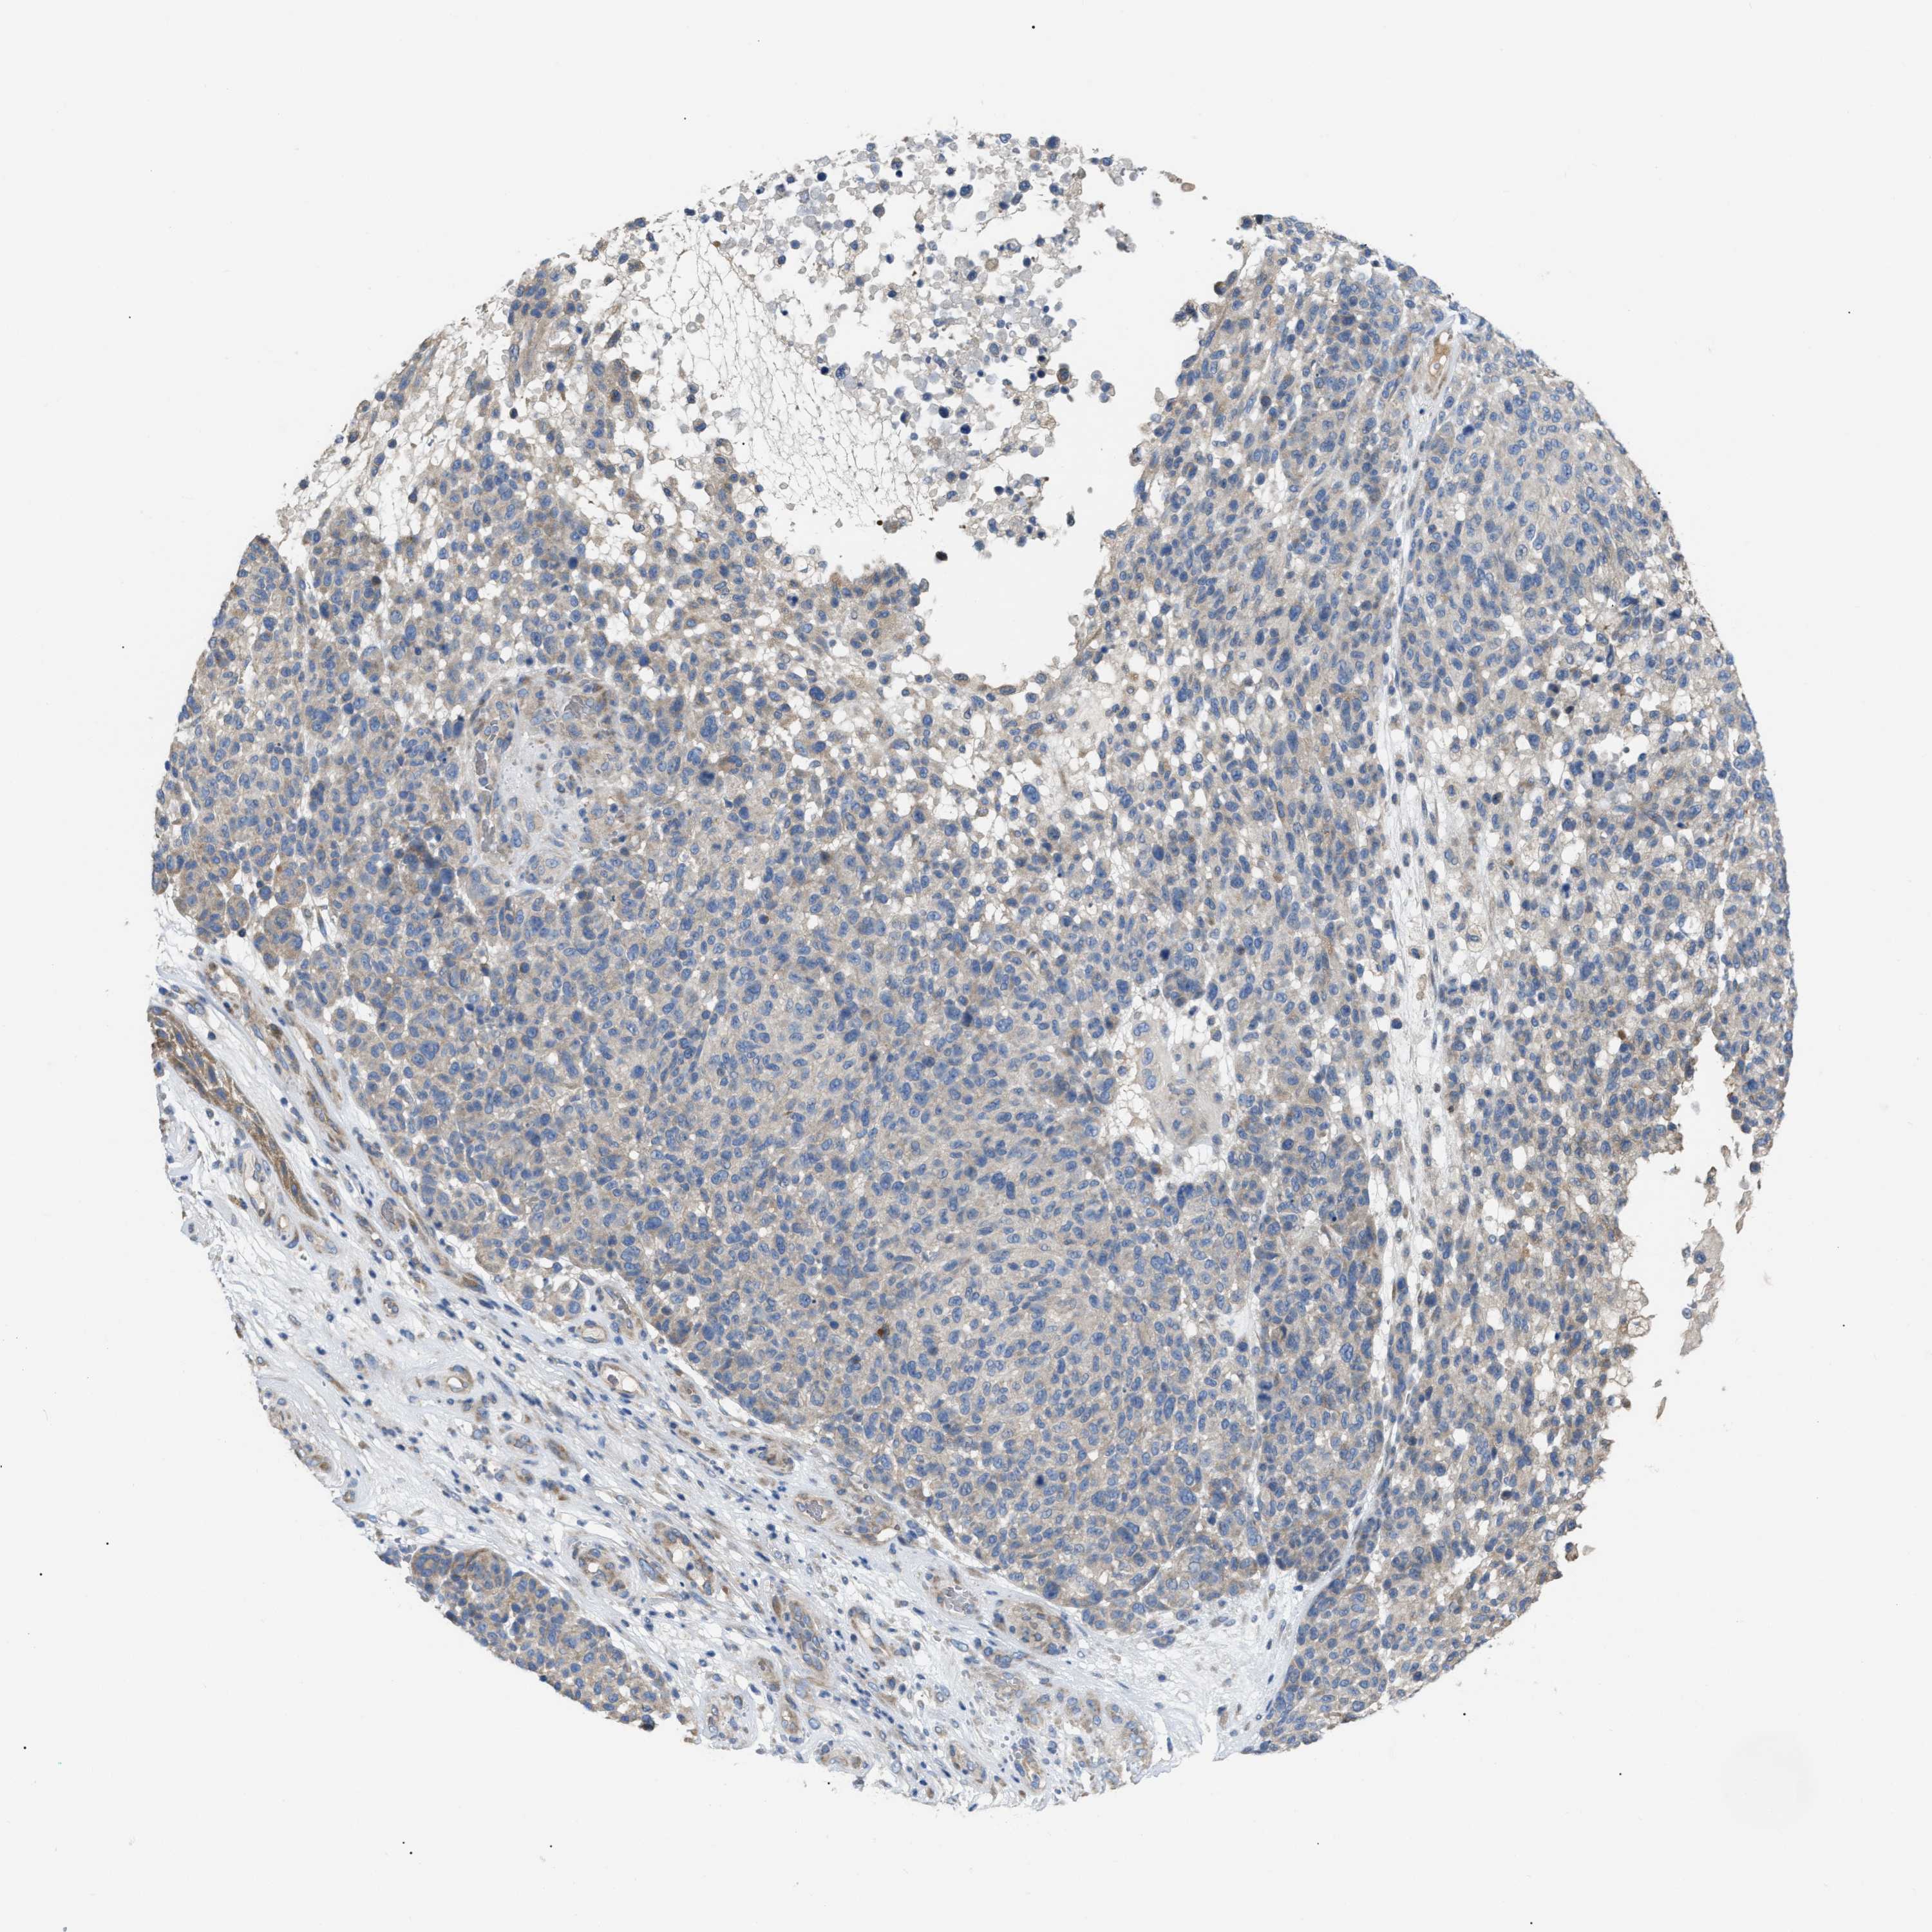

MELANOMA - Protein expressioni

A mouse-over function shows sample information and annotation data. Click on an image to view it in a full screen mode. Samples can be filtered based on level of antibody staining by selecting one or several of the following categories: high, medium, low and not detected. The assay and annotation is described here.

Note that samples used for immunohistochemistry by the Human Protein Atlas do not correspond to samples in the TCGA dataset.

Antibody stainingi

Antibody staining in the annotated cell types in the current human tissue is reported as not detected, low, medium, or high, based on conventional immunohistochemistry profiling in selected tissues. This score is based on the combination of the staining intensity and fraction of stained cells.

Each image is clickable and will lead to virtual microscopy that enables deeper exploration of all samples and also displays staining intensity scores, fraction scores and subcellular localization as well as patient and tissue information for each sample.

Antibody HPA018670

Antibody HPA019570

Staining

High

Medium

Low

Not detected

Intensity

Strong

Moderate

Weak

Negative

Quantity

>75%

75%-25%

<25%

None

Location

Nuclear

Cytoplasmic/membranous

Cytoplasmic/membranous,nuclear

Malignant melanoma, NOS

Malignant melanoma, Metastatic site